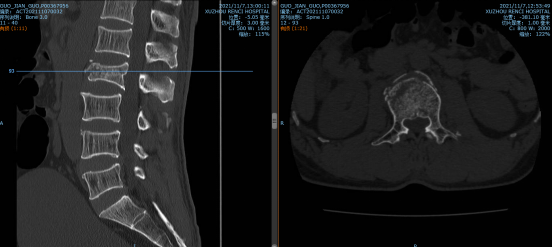

11月初山东的郭大叔如往常一样在厂里干活,突然设备掉落砸伤了其腰背部,当时他就不能动了,家人、同事连忙将他送到当地医院检查,结果ct显示大叔的L2椎体骨折。这可急坏了大叔的家人,家人找亲朋好友四处打听,得知betway在线登陆可以做脊柱微创手术,连夜带着郭大叔来我院就诊。

脊柱科孟磊副主任医师为大叔检查后,发现他不单单是腰椎骨折,还有胸骨体骨折、腰椎横突骨折、棘突骨折、右侧第3-5、8肋骨骨折伴有肺部挫伤以及胸腔积液。患者家属表示,大叔是家中的主要劳动力,请求孟医生一定要帮帮他们一家!孟医生手术团队决定采用机器人辅助下腰椎骨折复位内固定术。和传统手术相比,天玑骨科机器人辅助更安全高效,手术切口小、定位精确无误差、伤口小、疼痛轻、恢复快。

最终,孟磊副主任医师团队在天玑骨科机器人定位下,通过3D图像扫描规划手术中椎弓根螺钉的进钉点、置钉方向以及置钉深度。根据机器人系统导航,通过机械臂精准定位置钉位置,医生只在置钉部位切开约2cm切口,不损伤其它椎关节,保障神经安全和手术的有效性。